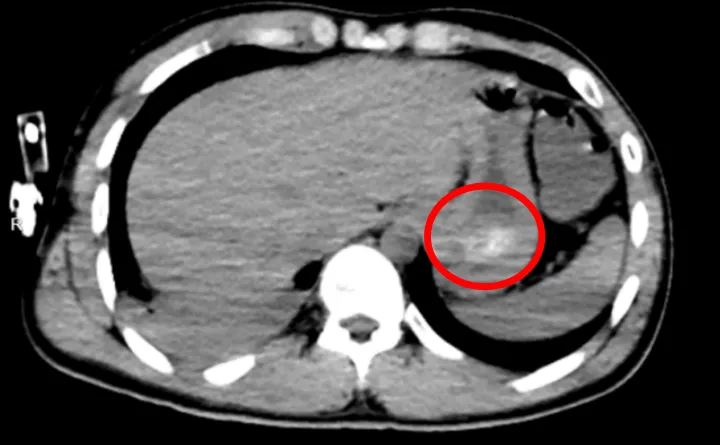

全腹CT结果验证这一判断:他的胃底可见大量团块状高密度影,正是那团凝结的药物;同时,胸部CT也提示,双肺出现渗出性病变,右肺下叶尤为严重,已经出现了吸入性肺炎。

也就是说,导致林浩昏迷不醒的——正是胃里还在持续释放毒性的药团,再叠加吸入性肺炎。

食管管腔里遍布黄色药渣残留,胃底更是被一大团质软易碎的黄色团块堵得严严实实,那正是150余片药凝结成的“药石”。